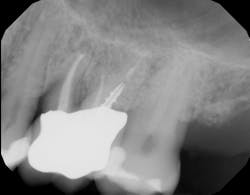

There is sufficient bone support around the remaining roots (at least 50% or more is needed) along with sufficient coronal tooth structure (figure 3).How does root amputation compare with other surgical procedures?

The prognosis is good for molar teeth treated with root amputation, provided case selection and treatment are performed properly. Fugazzottoreported 15-year cumulative success rates comparing molar root resection to molar implant placement, with survival rates of 96.8% for root-resected molars and 97.0% for molar implants.10 This study was done in private practice with proper oversight and case selection.Conclusion

Root amputation remains a viable treatment to save maxillary molars and can have long-term success rates equal to dental implant therapy (figures 9 and 10).Editor’s note: This article originally appeared in Perio-Implant Advisory, a chairside resource for dentists and hygienists that focuses on periodontal- and implant-related issues. Read more articles and subscribe to the newsletter.